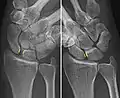

Dynamic instability: Increased scapholunate distance (between yellow lines) upon ulnar deviation of the wrist, but not otherwise.

Dynamic scapholunate instability visible upon clenching the wrist